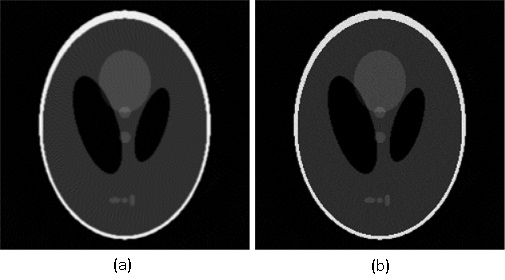

The iterative reconstruction algorithms for X-ray CT are typically compared to the filtered back-projection algorithm. As an example that we will use for comparison, consider the Shepp-Logan cross-section shown in Fig. 1, of size 250 by 250 pixels.

The corresponding sinogram is a matrix with 359 lines and 270 columns. For this set of parameters, the result obtained by the MATLAB implementation of the filtered back-projection algorithm is shown in Fig. 2.

Given the problems we have pointed out regarding the first randomized algorithm, we have focused on the results obtained by the second randomized algorithm. For the parameters that we have fixed above, the results obtained by running the second randomized algorithm with 125000 iterations are given in Fig. 4 and Fig. 5 (Fig. 4 (a) is Fig. 2, and Fig. 5 (a) is Fig. 3). In both cases, the correction is significant, and the result of correction is very close in terms of reconstruction quality to the result obtained by running each of the two analytical algorithms alone with full view of 360 projection angles. That is, the result shown in Fig. 4 (b) is comparable to the result shown in Fig. 6, and the result shown in Fig. 5 (b) is comparable to the result shown in Fig. 7, which means a reduction in the number of views of (in Figs. 6 and 7 the reconstruction is more homogeneous, but with more visible artifacts). From the experiments we have conducted, we have remarked that the number of views can be reduced up to about and the results are still comparable to the results obtained by the analytical algorithms with full view, provided an appropriate number of iterations is chosen.